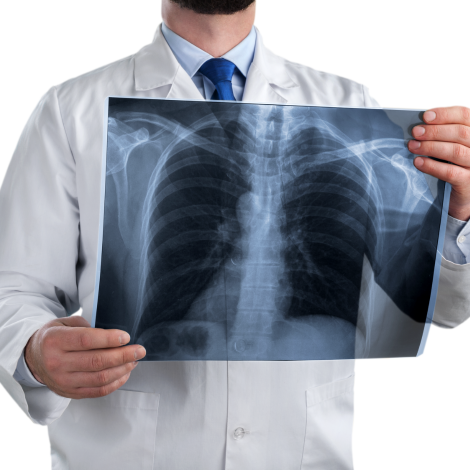

Chest X-ray

If you have symptoms such as feeling short of breath, a chest X-ray can help doctors find out if it’s caused by a heart or lung condition or something else. You would also have a chest X-ray done as part of routine health-check, pre-employment check or work up for any surgery.